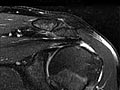

Magnetic Resonance Imaging (MRI) of the Shoulder

Magnetic Resonance Imaging (MRI) of the ShoulderSkip to the navigationTest OverviewMagnetic resonance imaging (MRI) is a test

done with a large machine that uses a magnetic field and pulses of radio wave

energy to make pictures of the shoulder. Muscles,